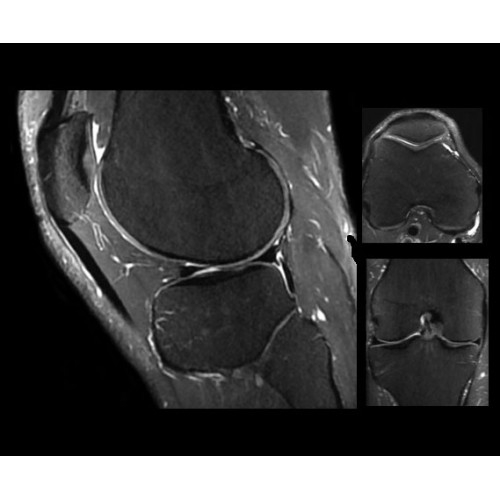

SIGNA PET/MR 3.0T — это гибридная система, в которой совмещаются две принципиально разные технологии — магнитно-резонансную томографию (МРТ) и позитронно-эмиссионную томографию (ПЭТ). Система отличающийся высокой чувствительностью и эффективностью и предназначена для диагностики в области онкологии, неврологии, кардио-васкулярных исследований, исследований воспалительных процессов.

МРТ-аппараты, Полуоткрытые аппараты МРТ, МРТ аппараты для животных